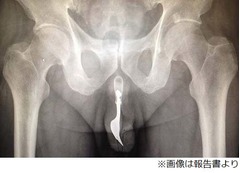

報告では男性が搬送されてきたとき、入り込んだフォークは完全に外から見えない状態だったとのこと。しかし、触るとフォークの形を認識できるほどしっかり尿道の中に収まっていたそうで、レントゲン検査で位置を正確に把握した医師たちは、すぐに男性に全身麻酔をかけた上で手術に踏み切った。除去の仕方については、いくつかの方法が検討されたものの、結局、大量の潤滑オイルを使って慎重に抜き出すやり方を選択。幸い特に大きな問題も起きず、フォークは無事に男性の体から取り出された。